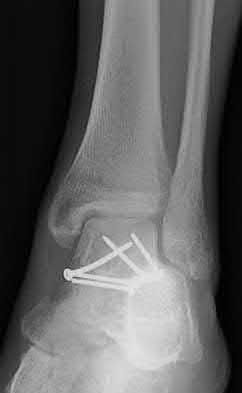

Figure A shows a patient after an open reduction and internal fixation of a bimalleolar ankle fracture.

Egol et al showed that by nine weeks, the total braking time of patients who had undergone fixation of a displaced right ankle fracture returns to the normal, baseline value.

Egol et al, also found that appropriate braking time returns at a point 6 weeks after initiation of weightbearing after treatment of lower extremity long bone and periarticular fractures, as examined with a driving simulator. No differences were seen in return of braking time between periarticular fractures and long bone injuries.